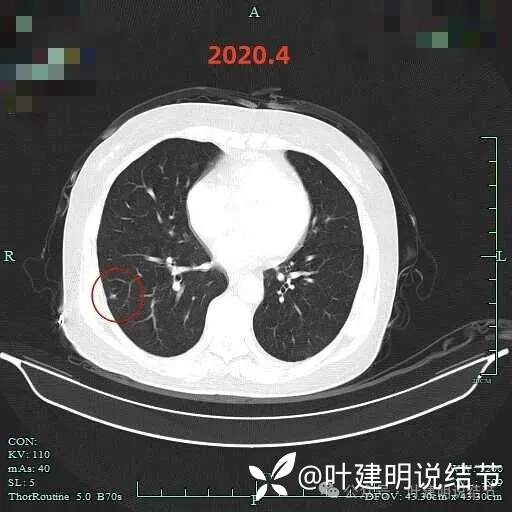

到了2020年4月,右下病灶表面略显毛糙,灶内密度稍不均,微小血管进入,整体轮廓较清。